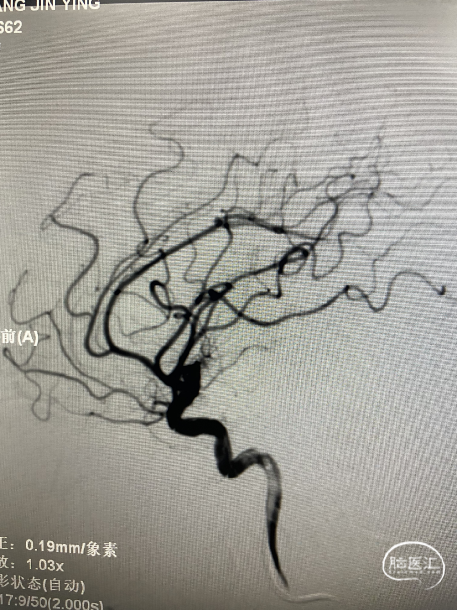

患者静吸复合全麻造影示:左侧颈内动脉交通段可见约5.5mm×3.0mm大小动脉瘤,瘤颈宽2.7mm,右侧大脑中动脉可见2.0mm×2.1mm大小动脉瘤,瘤颈宽1.8mm。右侧颈内动脉交通段可见约6.3mm×5.8mm大小动脉瘤,瘤颈宽4.2mm,左侧大脑前动脉A3段可见约1.8mm×1.8mm大小动脉瘤,瘤颈宽1.3mm。右侧胚胎型大脑后动脉。

术中三维所见

6F导引导管至于左侧C2段,在Synchro-0.014 200cm微导丝携带下将PROWLER SELECT PLUS微导管送至左侧大脑中动脉M2段,在ASAHI CHIKAI-0.014 200mm微导丝携带下将Echelon 10微导管送至瘤腔内。

路图引导下将4mm×12cm 3D弹簧圈(EV3)沿微导管置入动脉瘤腔内暂不解脱,沿支架微导管将4.5mmx22mm支架(Enterprise)置入左侧颈内动脉交通段。继续填入弹簧圈